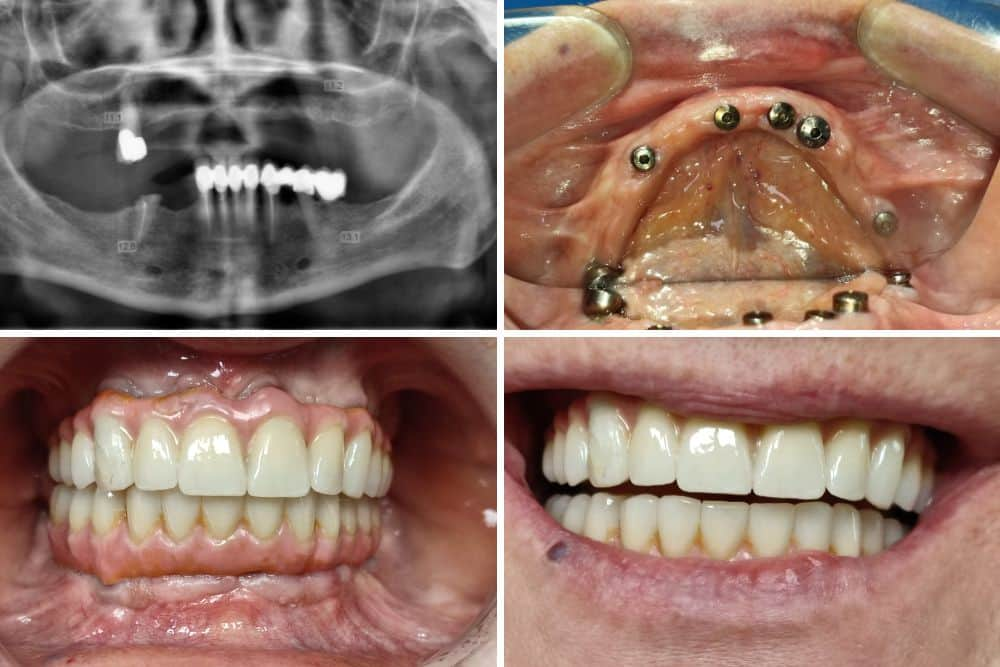

Pacijent Stomatološke klinike Dr Veselinović